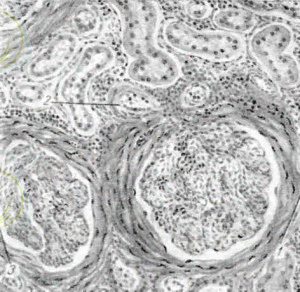

2. 2. Гистопрепарат. Шумлянский капсуласының гиалинозы

Микроскоптың аз өсуімен Шумлянскийдің капсуласында күрт өзгерістер байқалады. Капсула едәуір қалыңдатылған, эозинмен қызғылт-қызыл түске боялған кең белдеу пайда болады. Сақталған жасуша ядролары өте аз, мальпигиялық гломерулалардың қуысы тарылған.

2-сурет. Шумлянский капсуласының гиалинозы

1-гиалинді капсула, 2 - тамырлы гломерулус, 3-бүйрек каналы.

Микроскоптың орташа ұлғаюымен капсула кең, біркелкі боялған, біртекті жіптерден тұратындығын көруге болады, олардың арасында ұзартылған ядролары бар жасушалар аз болады.

Бүйректің интерстициясындағы тамырлардың қабырғалары да күрт қалыңдайды, олардың люмені тарылады. Эндотелий сақталған, оның астында интимде жиналған біртекті ақуыз массасы орналасқан. Ван-Гизон әдісімен боялған кезде Шумлянскийдің капсуласы, қан тамырларының қабырғалары, сондай-ақ өсіп келе жатқан дәнекер тін қызыл болады. Интерстицияның өзінде маңызды жасушалық инфильтрация байқалады.